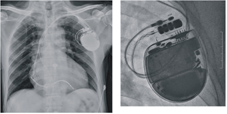

植入性心律去顫器(ICD)大小如同火柴盒,通常植入於鎖骨下方的位置

植入式心律去顫器監測心肌缺氧 體內心電圖監測: 心肌缺氧造成ST段變化